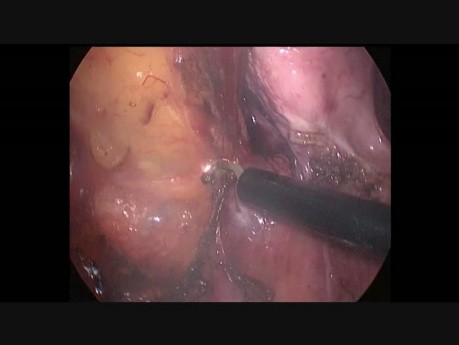

Laparoskopowa hemikolektomia prawostronna

Film przedstawia fragment hemikolektomii laparoskopowej. W części tej odnaleziono moczowód. Autorami filmu są: John H. Winston, III, M.D., MBA, FACS, FASCRS Wm. Cannon Lewis, M.D., FACS, FASCRS www.colorectalsurgeryservices.com...